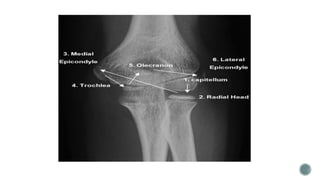

 Medial Epicondyle Apophysis Fractures

 Pulled Elbow Syndrome

 Lateral Condylar Fractures

 Capitellar Fractures

 Medial Condylar Fractures

 Lateral Epicondyle Apophysis Fractures

 Trochlea Fractures